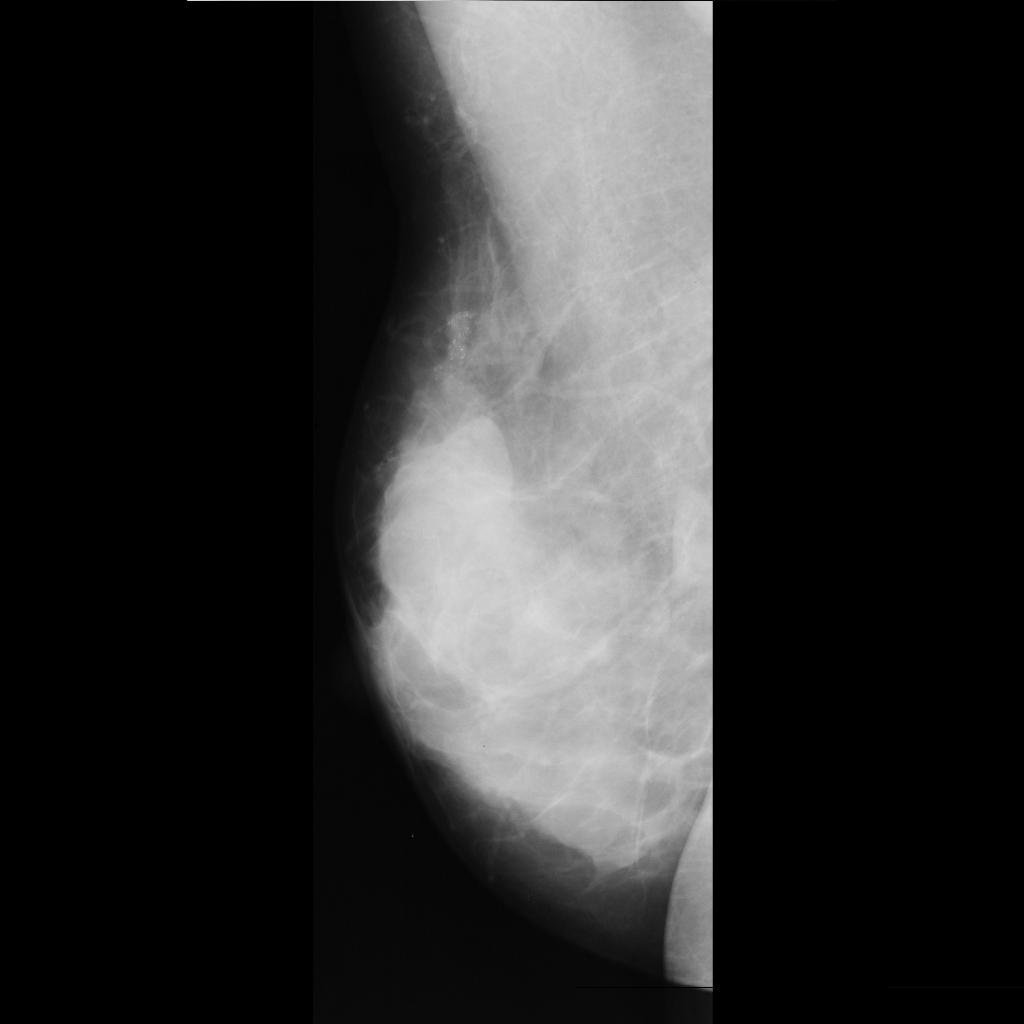

benign

malignant